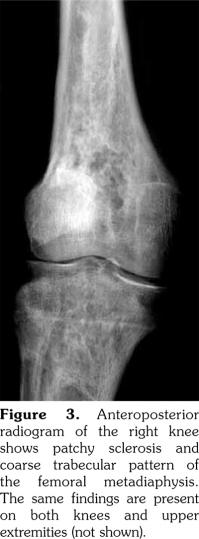

A 51-year-old male patient admitted to our outpatient clinic with complaints of flank pain and fatigue. He had a history of renal stones and peripheral arterial disease. He had a medically unmanageable hypertension. Blood pressure was 200/110 mmHg. Serum creatinine level was 1.2 mg/dL. He was evaluated with contrast- enhanced multislice computed tomography. Along with small calyceal stones, there was bilateral, quite symmetrical perinephric ''rind-like'' soft tissue infiltration. Right kidney was atrophic but still functioning without pelvicalyceal contrast excretion. The soft tissue infiltration obliterated both renal hila and caused proximal ureteral stenoses with mild calyceal dilation on the left side (Figures 1 and 2). Distally, the ureters were normal. Incidentally, abdominal aorta, common iliac arteries, proximal celiac trunk, and proximal renal arteries were noticed to appear “coated” with subtle perivascular tissue infiltration. An endovascular aortoiliac stent-graft was in place. He rejected any further diagnostic intervention after he presented with a blood creatinine of 2.2 mg/dL. He underwent an unenhanced computed tomography examination with the same findings before. Renal scintigraphy revealed a non-functioning right kidney. Perinephric soft tissue infiltration was considered as the differential diagnosis of ECD. Direct radiographies of the extremities were obtained. All of the long tubular bones showed diametaphyseal cortical and patchy medullary sclerosis reinforcing the diagnosis of ECD (Figure 3). The patient underwent right nephrectomy for the control of hypertension and a double-J stent was placed on the left side for the relief of ureteral obstruction. The nephrectomy specimen showed the typical histological features of ECD. Serum creatinine level dropped to the borderline values after the operation and his blood pressure was in the normal range with medications. The pathological analysis of the nephrectomy specimen revealed an inflammatory infiltrate formed by foamy histiocytes that were positively stained for CD68 and neutrophilic aggregates which confirmed the preoperative diagnosis (Figures 4 and 5). A written informed consent was obtained from the patient.

The histiocytic infiltrative process, as found in our case, may involve the retroperitoneum in approximately 29 to 68% of patients.(4,5) The soft tissue infiltrate around the aorta and its major branches can be misdiagnosed as arteritis, lymphoma or retroperitoneal fibrosis.(4) The process may lead to severe arterial stenosis and the consequences include cerebral ischemia, cardiac angina, mesenteric ischemia, or renovascular hypertension.(6-8) Adrenal glands, kidneys, renal arteries, ureters, and adjacent anatomical spaces may be involved in the process. Infiltration of perirenal space may extend to the pararenal space with irregular borders, thus will be given the name “hairy kidney”.(6) Extension to the renal sinuses and pedicles, proximal and distal ureters is possible and may cause obstruction and eventually, as in our case, compromise renal function.(8-10)

In our case, computed tomography findings suggested retroperitoneal fibrosis but the infiltrate did not involve the vena cava and the paraaortic infiltration was circumferential instead of sparing the posterior aspect of the aorta. Also, the perinephric infiltration was far more striking than the perivascular space which is inconsistent with retroperitoneal fibrosis. Therefore, the differential diagnosis consisted mainly of processes involving perinephric and perivascular spaces, namely, lymphoma, retroperitoneal fibrosis, and ECD. The diagnosis of ECD was strongly suggested with the radiographic findings of the extremities which revealed symmetrical dia-metaphyseal osteosclerosis.